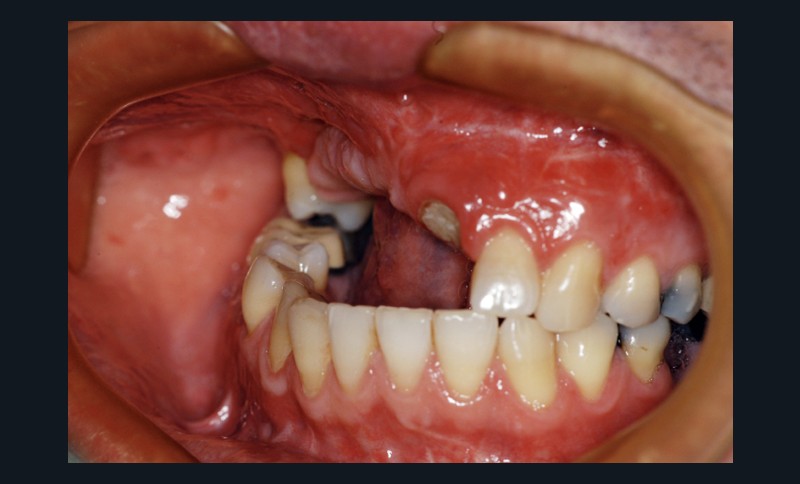

Car ce sont bien des situations cliniques exceptionnelles que ce conférencier a prises en charge, non pas seul, mais en constituant une équipe multidisciplinaire plus à même de relever les défis fonctionnels, structurels, biologiques et esthétiques en présence. Après avoir passé en revue les composants essentiels à l’obtention d’un sourire équilibré, Nadim Aboujaoude a évoqué les travers des traitements dits esthétiques mais conduits sans planification globale et qui engendrent des résultats disgracieux. Depuis de nombreuses années, l’engouement pour les solutions esthétiques ne faiblit pas. La divulgation médiatique des progrès technologiques et chirurgicaux réels encourage une part croissante de la population à recourir à des procédures souvent fiables, mais parfois portées au-delà des limites raisonnables. Ainsi, des traitements de médecine esthétique inadaptés engendrent un effet de « ligne de sourire basse » accompagné d’une exposition exagérée des incisives mandibulaires.

La demande de correction de cette anomalie esthétique incite les patientes à rechercher une compensation prothétique (à travers un abaissement des bords incisifs maxillaires visant à rendre sa visibilité au groupe incisivo-canin maxillaire) qui concoure à recomposer les rapports des étages de la face (en minorant l’étage inférieur et majorant l’étage moyen). La reprise de ces cas cliniques se révèle particulièrement délicate et repose sur une analyse rigoureuse des clefs esthétiques de l’harmonie du sourire et de son rayonnement au sein du visage.

Concernant le versant orthodontique des traitements multidisciplinaires, Nadim Aboujaoude intègre cette thérapeutique moins invasive à ses traitements multidisciplinaires sans rechercher une occlusion de classe 1 mais en privilégiant l’obtention de situations facilitant les solutions prothétiques, parodontales ou implantaires : en redistribuant et optimisant les espaces prothétiques, en corrigeant les malpositions dentaires, en remplaçant les dents compromises par les dents adjacentes, en harmonisant les contours gingivaux, en optimisant l’inclinaison des racines dentaires et en créant des volumes osseux favorables à la mise en place d’implants. À l’issue d’une présentation riche en prise en charge thérapeutique de cas complexes, le conférencier a clairement démontré que toute solution thérapeutique ne peut se concevoir et s’établir que dans une logique multidisciplinaire axée sur la concertation.